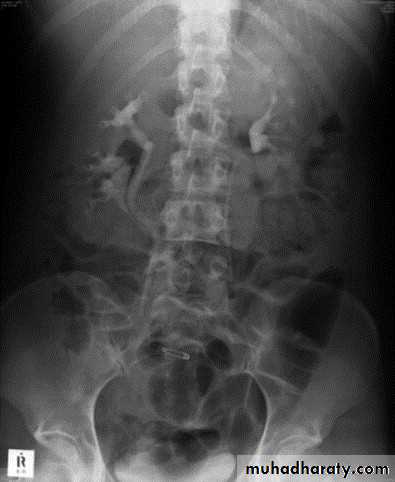

:*Ectopia vesica :-bladder located at low position with separartion of symphysis pubis.